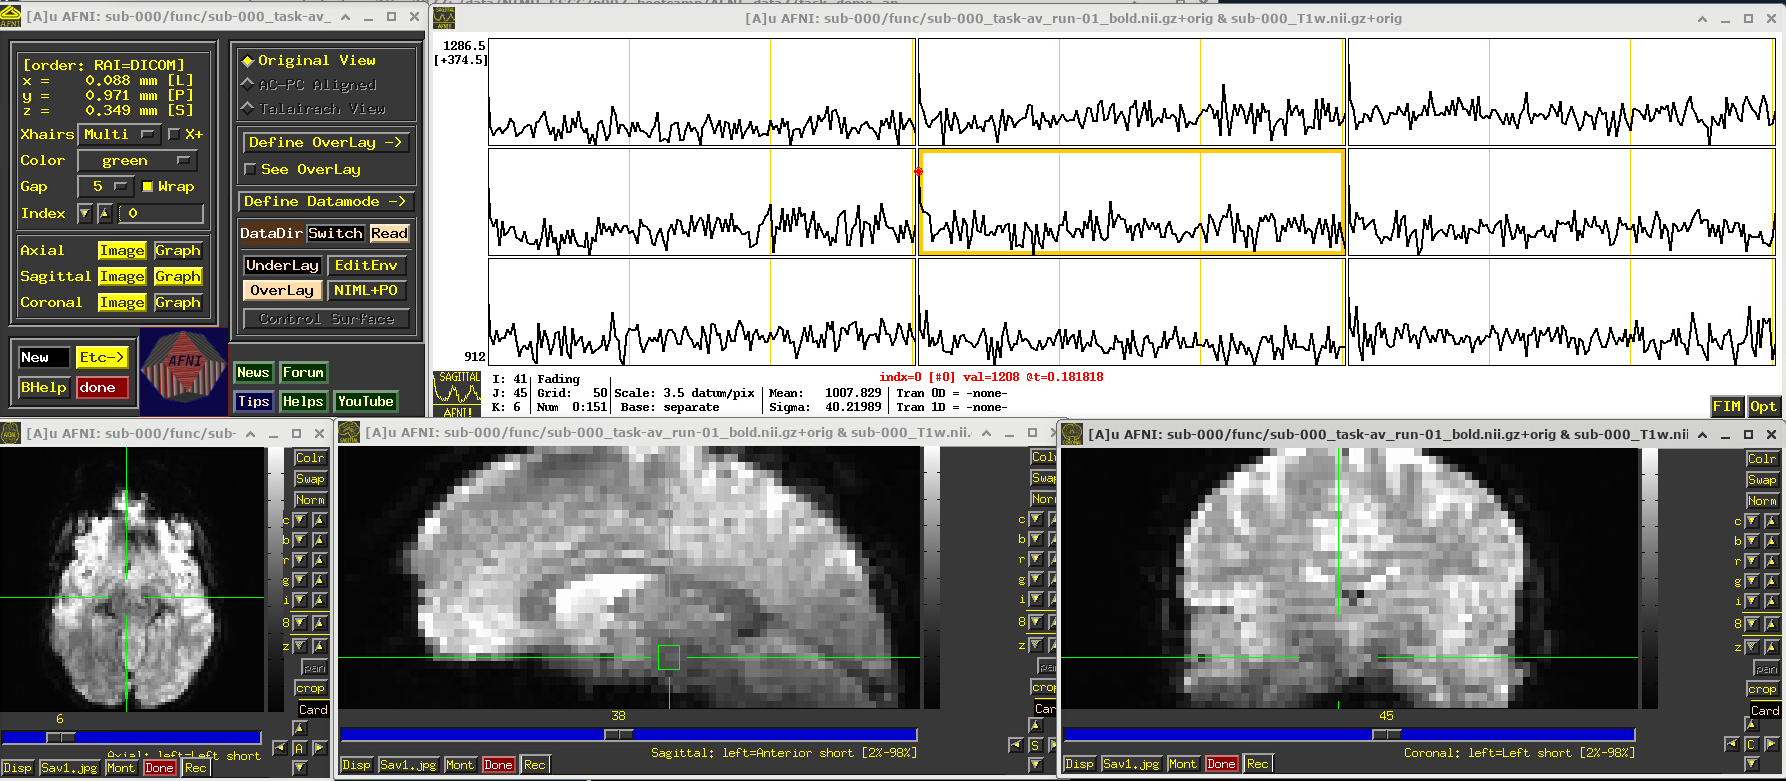

EPI feature: task response

The task performed during this FMRI scan was an audio-visual one. So, let’s check out how things look in the visual cortex. Well, see see some notable patterns, such as at the location (x,y,z) ~ (16, 78, 3.3), as below. While the earlier-noted motion and pre-steady state spikes apparent, we now see some very regular pattern of hills. And indeed, these are signatures of task-related BOLD response for this block design paradigm (we could load the idealized response time series into the graph viewer, too, to help verify this).

Specifically, this paradigm has the start of a block that contains either a blurred or clear visual component every 30s and a duration of 20s, so seeing regular response in the visual cortex is not unexpected. The fact that we see a few time series in this graph montage with the task signature reflects our spatial sampling: the voxel edges are roughly the same diameter as GM cortex. Notice also that the response shapes aren’t perfectly rectangular—the BOLD response is not on/off, but has a ramp up and ramp down—and that notable plus/minus noise bumps are still present.

Later, we will look at performing real processing to get a more detailed description of task responses: quantifying each stimulus class, perhaps comparing them (i.e., evaluating their “contrast”), trying to boost their signal-to-noise ratio while also reducing spikes and other noise features. That is the job of the real processing.

# Display a screenshot of the AFNI GUI with the first EPI run loaded

IPython.display.Image(filename='example_snapshots/img_03_afnigui_epi_r01_taskresp.png')

../_images/df242a56362284883d4e5b72322ff8de8574fb812b73727711a90463314798b7.png